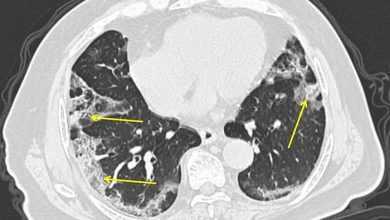

دراسة جديدة: الآشعة المقطعية قد تُساعد الأطباء في تشخيص الإصابة بفيروس كورونا في وقت مبكر

أشارت دراسة حديثة إلى أن الآشعة المقطعية (CT scan) قد تُساعد الأطباء في تشخيص المرضى المُصابين بفيروس كورونا المُستجد بشكل…